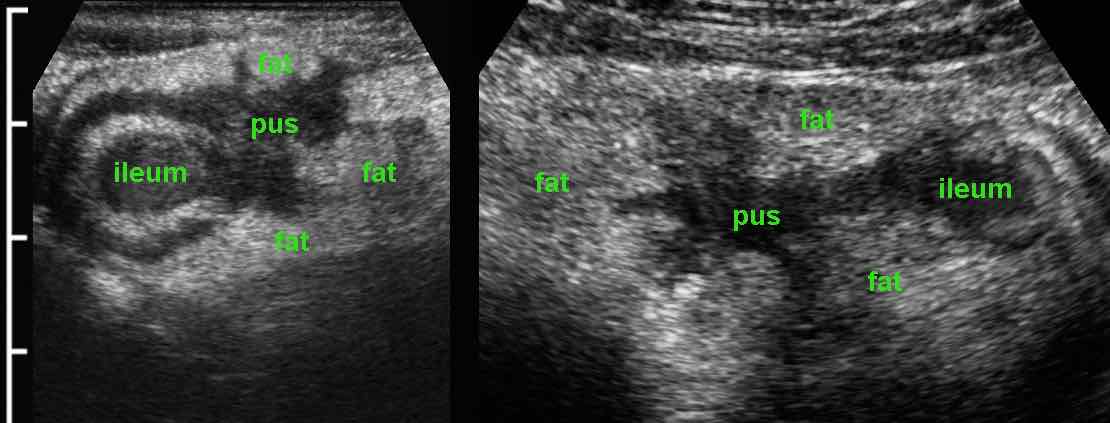

Áp xe

Hồi tràng tận đang viêm hoạt động với một vùng giảm âm có ranh giới vừa phải nằm ngoài thành ruột, được bao quanh bởi mô mỡ viêm, cho thấy sự hình thành đường xoang và áp xe.

Hai bệnh nhân có áp xe Crohn gần hồi tràng.

Lưu ý rằng áp xe trong bệnh Crohn thường nhỏ và xẹp.

Giải thích cho hiện tượng này là các áp xe này thường có thông nối hở với lòng hồi tràng, cho phép mủ thoát ngay vào lòng ruột khi áp lực tăng lên.